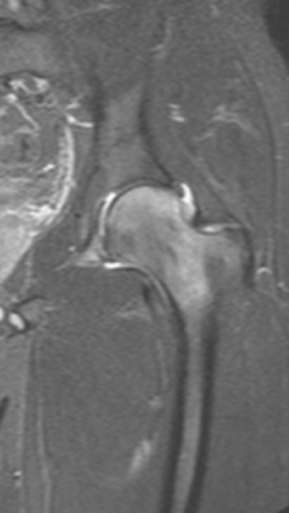

Асептический некроз коленного сустава

4 процедуры ФДТ, 9 процедур MBST, 15 процедур ИПМТ

Параметры изменяются в зависимости от процедуры

Дата публикации: 22.08.2025 14:27:03

3 процедуры ФДТ, 9 процедур MBST, 15 процедур ИПМТ

Дата публикации: 22.08.2025 14:26:54